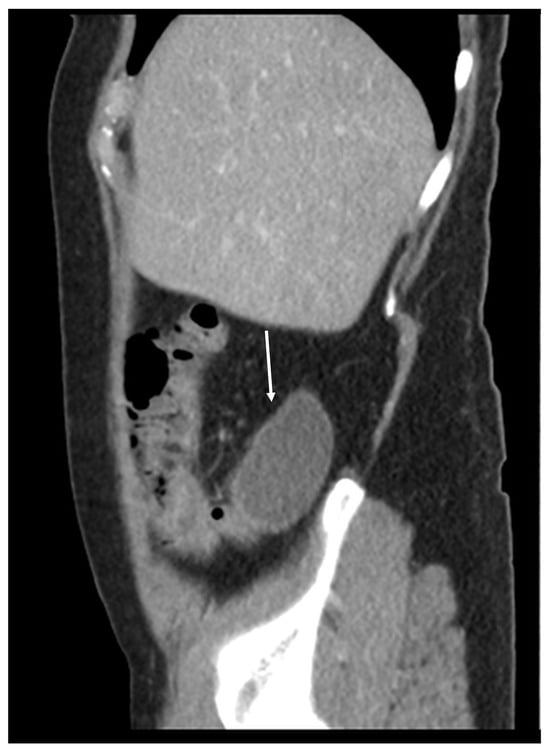

Figure 11, Figure 12, Figure 13, Figure 14 and Figure 15. Advanced stage of the disease. The abdomen is full of tumors and mucin. Typical signs are heterogeneous or hypodense masses in the form of lobules often with septa, which could be enhanced by contrast and could be associated with calcifications.

Patients with a misdiagnosed rupture of the mucocele may develop pseudomyxoma peritonei. It is characterized by the presence of an abundant gelatinous substance in the abdomen. Diffuse, progressive, and abundant mucin-containing tumor cells are typical of this disease [2] (Figure 11, Figure 12, Figure 13, Figure 14, Figure 15 and Figure 16). The interval between rupture and advanced disease is several years. In our clinical series, the interval was about 5 years. In the literature, we found a wide range of this interval from 12 months to 10 years [9,10]. The natural history of PMP revolves around the “redistribution phenomenon”, whereby mucinous tumor cells accumulate in the Douglas pouch, in the diaphragm (more on the right), and the small and large omentum (Figure 17). The small intestine is less involved [4]. Pseudomyxoma peritonei is a slowly progressing disease, which fills the peritoneal cavity over time. There are several classifications of pseudomyxoma. The most commonly used is the PSOGI classification [2]. Mucinous accumulation progresses to malnutrition, bowel obstruction, and respiratory compromise. Rarely, the tumor may spread to the pleural cavity. This has been described in 5.4% of cases. It may occur spontaneously or as a result of diaphragmatic injury during cytoreduction [8,11].

Figure 11. CT, venous phase, axial plane.

Figure 12. CT, venous phase, coronar plane.

Figure 13. CT, venous phase, axial plane.

Figure 14. CT, venous phase, coronar plane.

Figure 15. CT, venous phase, sagittal plane.